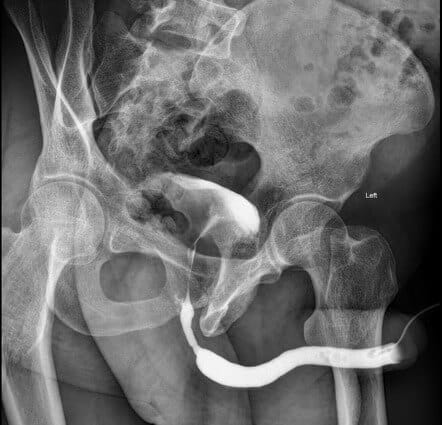

- Chụp niệu đạo-bàng quang ngược dòng hay cả 2 chiều xác định: vị trí và mức độ hẹp, lỗ dò hay túi thừa, sỏi ang quang, ang quang chống đối, cột hõm, túi thừa.